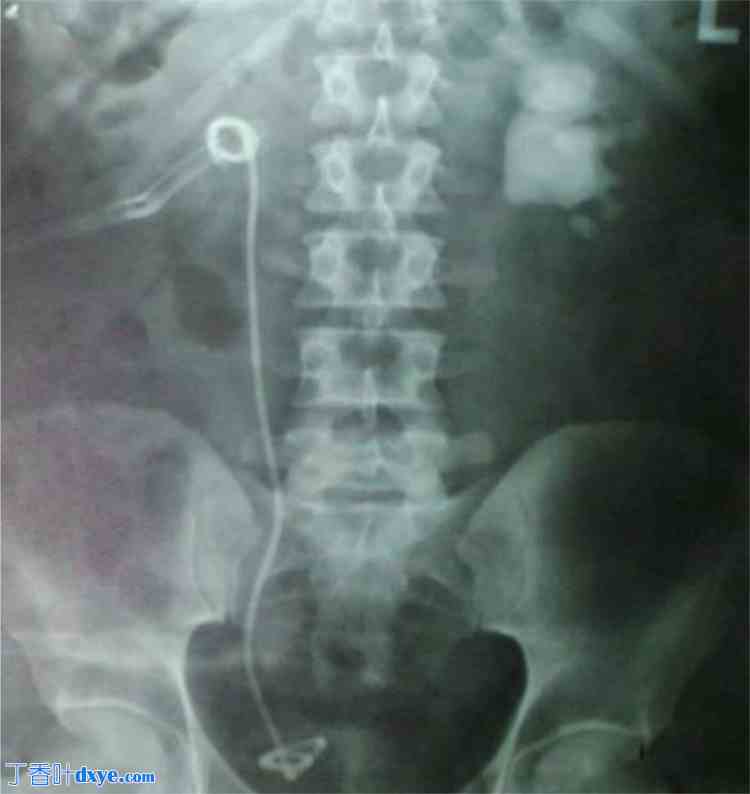

一名 50 岁男性,已知患有双侧梗阻性肾结石,因双侧腰痛入住泌尿科病房。疼痛剧烈,右侧疼痛更甚,并伴有多次呕吐。一周前,患者因右肾结石接受了一次 ESWL 治疗。基线检查显示白细胞计数异常,为 18,000/微升(正常范围为 4500 至 11,000/微升),中性粒细胞计数为 89%,淋巴细胞计数为 5.3%。肾功能检查也异常,血清尿素水平为 40 mmol/L,血肌酐水平为 270 μmol/L。完整尿液检查显示脓细胞(5-10/HPF)和红细胞(10-20/HPF)。其余实验室检查未见异常。腹部超声检查显示右肾上极有一个约 1 × 1.2 cm 的结石,导致右肾盂肾盏系统和输尿管中度扩张。右侧输尿管远端有几个回声灶,产生后部声影。靠近右腰大肌的肾周间隙有一个约 100 mL 的无回声积液。在左肾盂处发现了一个 1.6 × 3.8 cm (AP x TR) 的大结石,导致肾盂肾盏系统轻度扩张。还进行了腹部 NCCT 检查,显示右侧肾积水,输尿管扩张,似乎与靠近右腰大肌的肾周间隙中 CT 密度为 6 Hounsfield 单位 (HU) 的小块低密度液体积液相沟通(图 1)。还观察到明显的邻近炎性条带。结合1周前右侧ESWL病史,诊断为右侧近端输尿管穿孔,并形成尿瘤。右侧远端输尿管邻近S1椎骨延伸至尾骨处可见多枚结石碎片排列,呈石街状,最大的约1.5×1.5cm,Hounsfield单位(HU)为1938年(图2)。这些结石碎片是ESWL的另一个并发症。肾盂内可见一大型鹿角状结石,大小约1.6×3.0×3.7cm(AP×TR×CC),CT密度为746HU,导致肾盂肾盏系统中度扩张。左肾上极可见一结石,大小约为 1.01 × 1.5 × 1.9 cm (AP × TR × CC),CT 密度为 361HU;右肾上极亦可见一结石,大小约为 1 × 0.9 × 0.8 cm (AP × TR × CC),CT 密度为 980 HU(图 3)。

图 1.

(A、B) 普通 CT 腹部平片(横断面轴向视图)显示肾周腔内边界清晰的低密度液体(绿色箭头),并伴有沿右侧髂腰肌的液体流向。左肾盂内可见一大型结石(黄色箭头)。